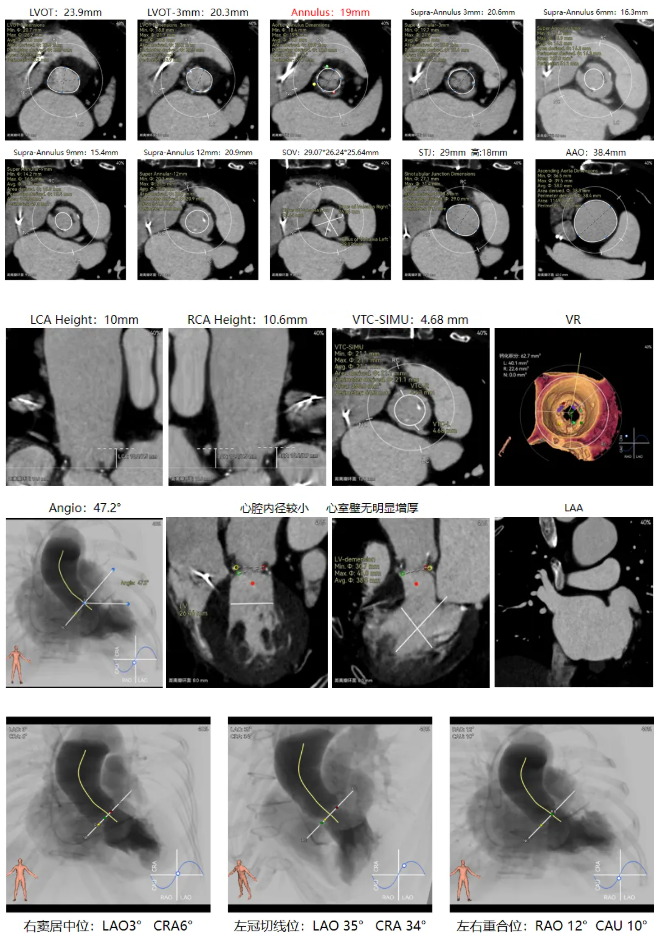

修建成教授 南方医科大学南方医院(点击查看专家详细简历) 直面瓣膜衰败,选对每一步护心路:前不久的ESC会议重磅发布瓣膜指南更新,将TAVR的患者年龄下调到70岁,且整体治疗理念迈向终身管理。该患者经历过一次外科手术,在人生70岁的当口,因生物瓣衰败再度面临 “心” 之困境,选择总是人生的一个重要课题,患者需要更微创的疗法、更耐久的瓣膜,医学的进步都是在主动探索中往前推进的,我们遵从患者的选择,不再被动应对衰败,而是主动定义瓣膜生命周期的边界。 手术一切按照既定的预演完成,术后患者情况良好,这不仅是一台手术的成功,更是将复杂瓣膜治疗推向 “精准化、耐久化” 新境序章,从瓣膜释放的瞬时血流动力学到远期抗钙化性能的预判,每一个参数都在诉说对长效生存的敬畏! 崔凯教授 南方医科大学南方医院(点击查看专家详细简历) 万千临床难题,唯提纲挈领方得始终:生物瓣衰败、心脏腔室小,这些问题都给手术添了不少难点。我始终觉得,需根据患者情况定手术方案,选择最合适的器械,综合考量:全新上市的预装干瓣开启了瓣膜心时代,预装技术让瓣膜装配标准化,规避了装载可能存在的肉眼不可见的损伤,干式储存技术规避了传统湿瓣的储存条件的钙化源头。可以说,为瓣膜的耐久性本身又增添了砝码。 对于衰败后的70岁患者,需要考量其长期耐久性问题,全新的产品需提前熟悉其产品特性;实践创新是心里装着对生命的敬畏,才能在复杂手术里找到办法。手术刀处理的不只是病,更是在跟时间赛跑,帮患者找希望。我们始终在找能让患者长期好好活下去的最好办法! 患者病史 现病史:患者近1月余前开始出现活动后胸闷、气促,爬楼、快走即可出现,休息后数分钟可缓解,至我院查心脏超声,提示:主动脉瓣生物瓣置换术后;主动脉瓣位生物瓣前向血流速度增快;左房增大,室间隔与左室后壁增厚,左室舒张功能降低,右房、右室内起博器电极线存留,二尖瓣返流轻中度,三尖瓣返流轻中度,肺动脉高压,心包积液(微量) 既往史:平素身体一般,有高血压1年,规律服用氨氯地平降压,有风湿性心脏病史,2011年行主动脉瓣生物瓣置换术;2011年植入双枪起搏器,2019年更换起搏器电池 超声提示: 主动脉瓣生物瓣置换术后;主动脉瓣位生物瓣前向血流速度增快,提示狭窄 左房增大,室间隔增厚,升主动脉增宽 右房、右室内起搏器电极线存留 三尖瓣反流(中度)二尖瓣反流(轻度) 肺动脉高压 左室射血分数正常 术前CT 生物瓣衰败ViV,原瓣膜内径19mm,LVOT23.9mm,靠原有框架锚定; 双侧冠脉开口高度可,窦部空间较大,VTC-SIMU:4.68,无冠脉风险;心脏角度47.2°; 心腔内径较小,心室壁无明显增厚,术中有循环崩溃可能; 右侧髂总动脉处有散在钙化,外周双侧入路无明显迂曲,双侧内径可,低分叉,主动脉弓距弓角条件良好; 手术策略:推荐右侧股动脉为主入路;生物瓣衰败ViV;球囊不预扩,22mm球囊后扩,预装可回收AV23主动脉瓣膜,瓣下5mm初始定位释放,工作位充分评估,符合释放要求后无张力释放 手术过程 最终造影 术后即刻探查超声平均跨瓣压差10mmHg。 术后患者当天下地,48小时出院 Prostyle A®预装干瓣——助力临床最优化解决方案: 1.平衡收腰:该患者生物瓣环较小,瓣膜型号需计算精准,Prostyle A 23号瓣膜平衡的收腰设计,兼顾血流动力学与冠脉安全; 2.柔顺过弓:较细的输送器尺寸+亲水涂层,在入路存在钙化的情况下,也能安全通过,过弓顺利,显著降低了血管并发症风险; 3.预装干瓣 便捷顺安:金仕生物专利抗钙化技术运用纳米技术去除组织内的细胞碎片和磷脂,封闭游离醛基,从根本上阻断了瓣膜钙化的多项因素,显著提升了瓣膜的耐久性;同时,相比较传统戊二醛保存方式,干式存储最大限度的保留心包的亲水亲油平衡,还原组织天然曲柔性,进一步保障了瓣叶开合,保证长期耐久性; · END ·

主动脉根部造影